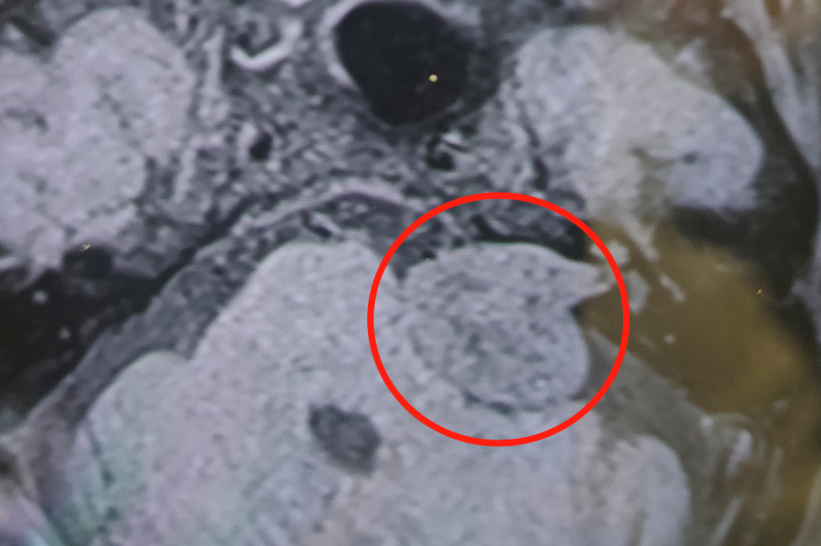

最近几年,卢大爷察觉自己的左耳听力越来越差,后来几乎完全听不见声音了。到医院一检查,发现肿瘤悄悄变大了,从原先的 1 厘米增大到了 3 厘米。

「肿瘤如果进一步增大,会继续压迫颅神经甚至是脑干,出现面瘫、瘫痪甚至昏迷等危险。」接诊的副主任医师张旭春反复查看、对比了患者近几年的检查报告,建议尽快手术。